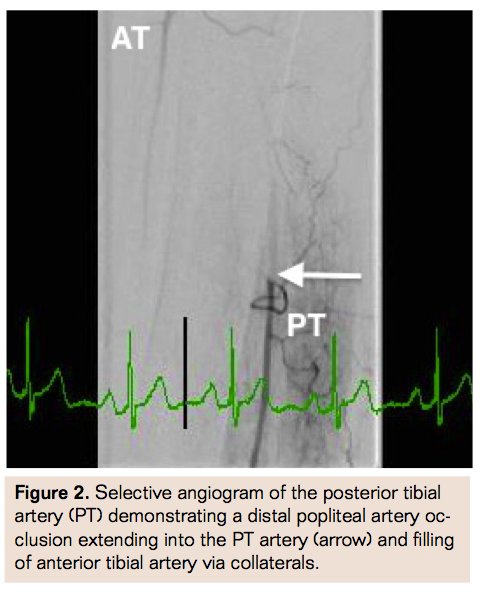

Due to the lack of contralateral CFA access secondary to prior bleed and covered stent placement, history of chronic thrombocytopenia, and increased risk of recurrent access bleed with antegrade access, the decision was made to obtain retrograde pedal access for revascularization. Using ultrasound guidance and a micropuncture access kit (Cook Medical), a 6 Fr sheath was placed in the right posterior tibial (PT) artery (Figure 1). Selective angiogram through the transpedal sheath confirmed distal popliteal occlusion extending into the PT with collateral filling of the anterior tibial artery (Figure 2). The popliteal occlusion was crossed using a glidewire and support catheter into the proximal SFA. Selective angiogram from this segment confirmed occlusion of the SFA at the distal edge of the previous stent (Figure 3). Rheolytic thrombectomy (Medrad Interventional) was performed through the occluded segment followed by balloon angioplasty with improvement in flow and small residual distal stent edge dissection (Figure 4). A Supera self-expanding stent (Abbott Vascular) was placed in overlapping fashion at the distal SFA stent edge with excellent angiographic result (Figure 5) and brisk runoff into the PT (Figure 6). Hemostasis was achieved in the posterior tibial artery access site using a RadAR compression device (Advanced Vascular Dynamics) (Figure 7). The patient was discharged home the following day with dual antiplatelet therapy regimen for an indefinite duration.